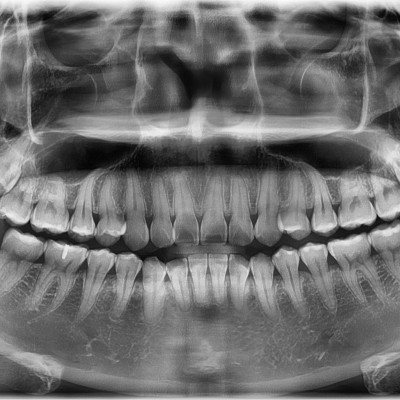

매복사랑니 발치 구강외과전문의가 직접 발치합니다.

작성자 이턱이 작성일 01-15 조회 27